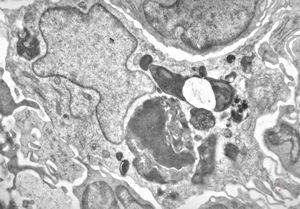

M, 43y. | myeloid leukemia

M, 43y. | myeloid leukemia … Auer bodies

M, 43y. | myeloid leukemia … Auer bodies

M, 43y. | myeloid leukemia … Auer bodies